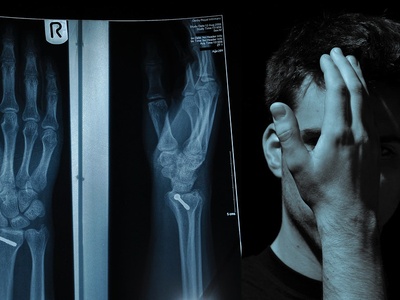

| Open Reduction Internal Fixation (ORIF) | Orthopedic/Trauma Surgery | Align/Fix | Open |

Open Reduction Internal Fixation (ORIF)

Surgical realignment and stabilization of fractured bones using plates, screws, or rods.